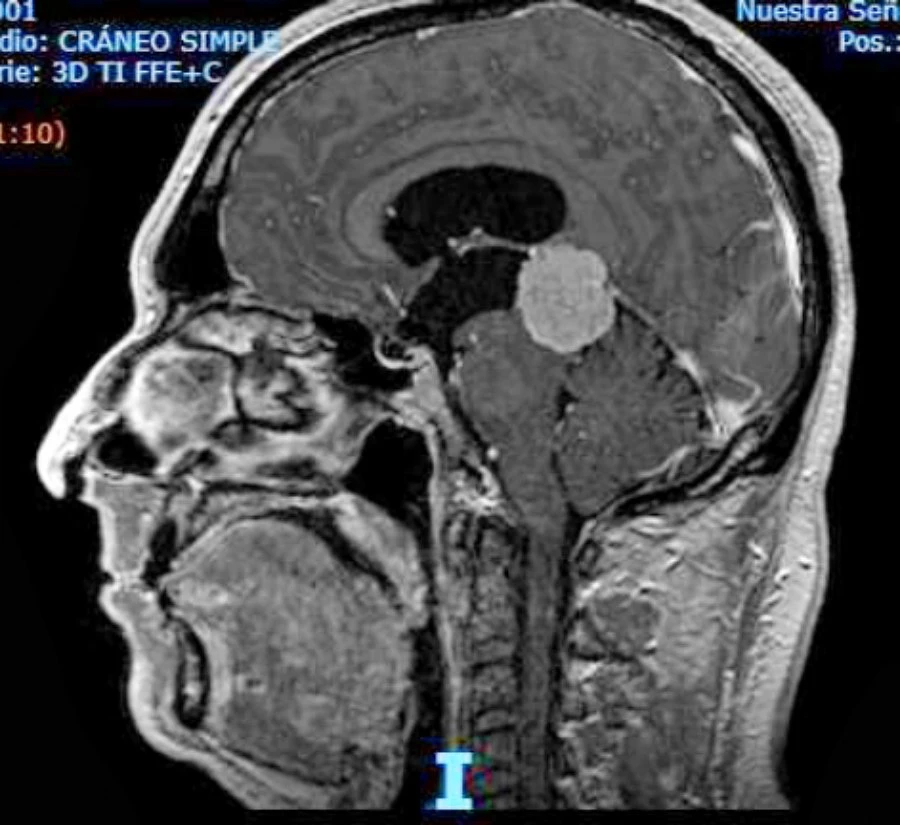

RESONANCIA MAGNÉTICA. ESTUDIO DE CIRCULACIÓN: Es relativamente fácil con la resonancia magnética hoy día, sobre todo porque hay resonancias de muy alto standing que acaban estudiando la circulación de líquido cefalorraquídeo a través del acueducto de Silvio.

Hallazgos en Resonancia Magnética – Índice de Evans y Ángulo Calloso

La resonancia es realmente una herramienta muy precisa para hacer el diagnóstico:

Edema transependimario: Primero porque se ve el edema transependimario, que se ve como esta zona blanca alrededor de los ventrículos.

Ángulo calloso: Después porque hay unos ángulos que se pueden medir. Este ángulo que es agudo, menor de 90º, es porque el globo ventricular, como esta estructura del cuerpo calloso es muy fija, lo que va a hacer el aumento de presión de los ventrículos es cerrarlo sobre esa estructura.

Índice de Evans: Y después también hay un índice que es la relación entre toda la corteza cerebral de esta longitud y la longitud del ventrículo.

Aparte de eso se puede acabar haciendo estudios muy sofisticados de cómo circula el líquido cefalorraquídeo por el acueducto, de manera que se puede acabar teniendo una clara idea de que estamos ante una hidrocefalia arreabsortiva.